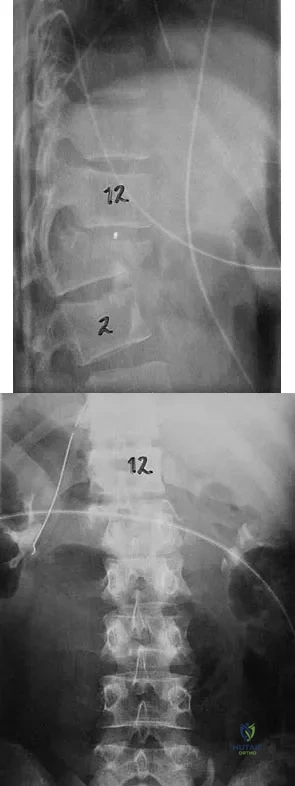

Figures 27a and 27b show the radiographs of a 32-year-old woman who was involved in a high-speed motor vehicle accident. She is neurologically intact. After stabilization and assessment, treatment should consist of